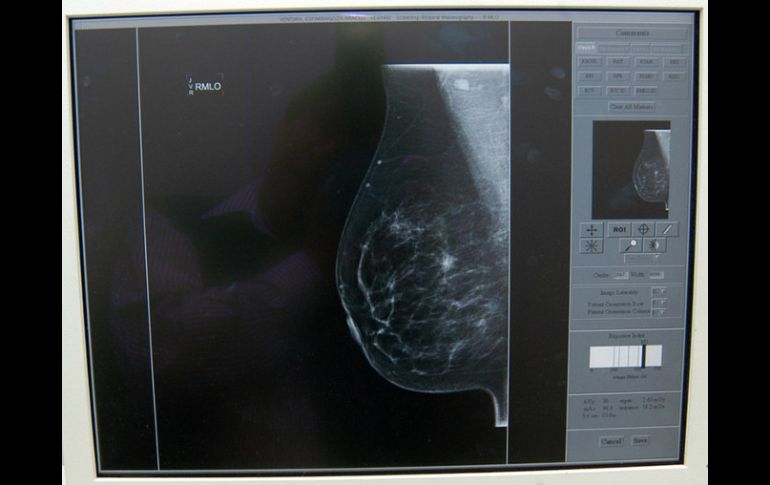

El IMSS cuenta con acciones específicas para la prevención, la detección y el control del cáncer de mama. ARCHIVO /

Detalló que en la actualidad el IMSS cuenta con acciones específicas para la prevención, la detección y el control de ese padecimiento, como son la promoción a la salud.

La autoexploración mamaria cada mes, a partir de los 20 años y hasta los 69 años de edad, sin omitir la revisión clínica de la glándula mamaria de los 25 a los 69 años y la mastografía cada dos años de los 50 a los 69 años, aunque se aconseja desde los 40 años, en caso de antecedentes familiares de este mal.